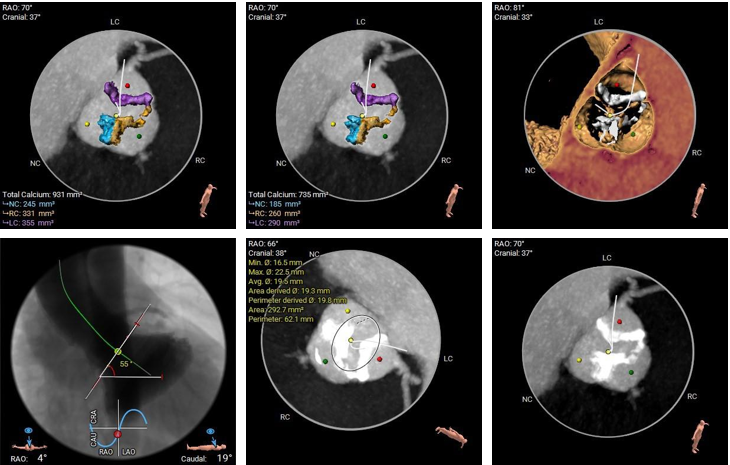

type1型二叶式主动脉瓣,R-N窦纤维钙化融合嵴,瓣叶轻度增厚伴重度钙化,左冠窦瓣叶钙化较重;LVOT呈敞口型;左冠脉开口高度较低,右冠脉开口高度尚可,左冠切线位瓣叶长度>冠脉开口到瓣叶附着缘距离;瓦氏窦、窦管交界内径、升主动脉内径正常;左室腔内径尚可、心室壁未见增厚;瓣环平面与水平夹角为55°,主动脉弓夹角、弓距尚可,升主动脉未见明显扭曲;主动脉弓、降主动脉下段、双侧髂总动脉可见散在钙化斑块,左侧髂动脉轻度扭曲,股动脉穿刺处未见钙化、狭窄,入路血管直径尚可。

冠脉阻挡风险评估

钙化及瓣环水平夹角评估